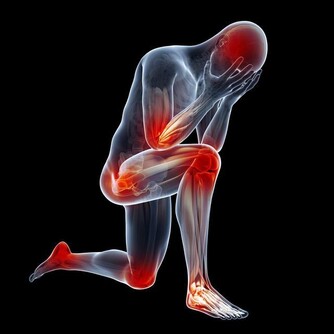

注意:這7種藥會讓尿酸升高,痛風發作

目前,患痛風的人越來越多,尤其是很多年輕人,不健康的生活習慣導致尿酸值越來越高,痛風發作的時候嚴重影響生活質量。然而,很多的痛風患者只是在盲目的降尿酸,並沒有弄清楚自己的尿酸為什麼會高,

如果你生活健康,沒有大量攝取啤酒、動物內臟、海鮮、濃茶等,最後尿酸值還是居高不下,還有一個重要的原因是——藥物性痛風,即很多藥物能夠導致尿酸高,今天就讓我們一起了解一下。